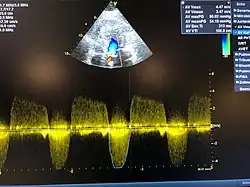

Kombiniertes Aortenklappenvitium mit hochgradiger Aortenklappenstenose